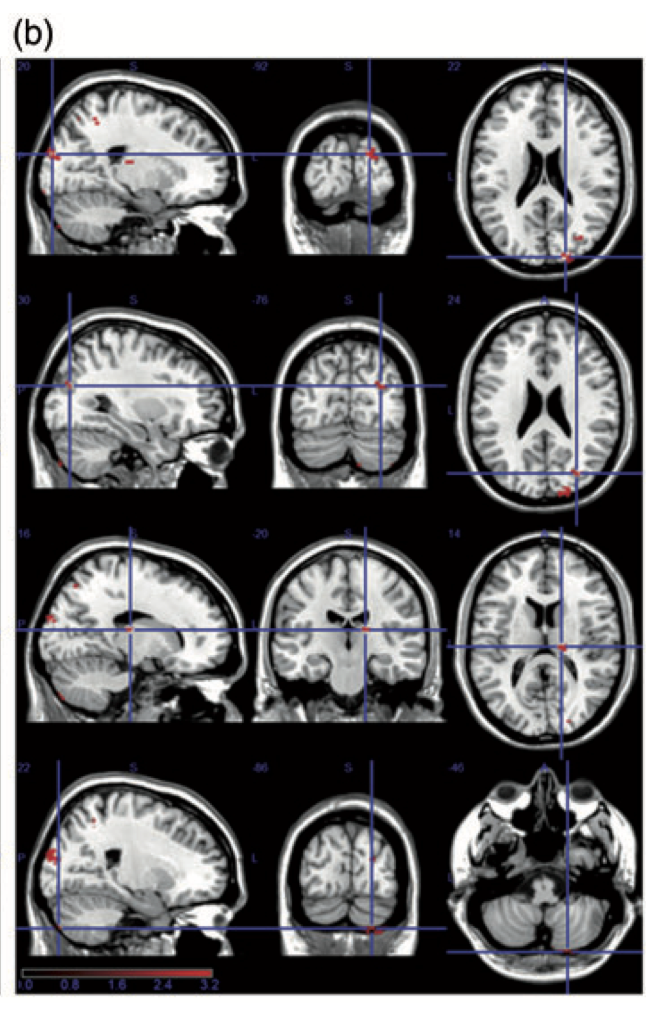

完全無料!上頭頂小葉機能を図解で解説。 上頭頂小葉について 上頭頂小葉と姿勢機能 左右の上頭頂小葉機能別 前頭葉と感覚野と上頭頂小葉の関係 まとめ